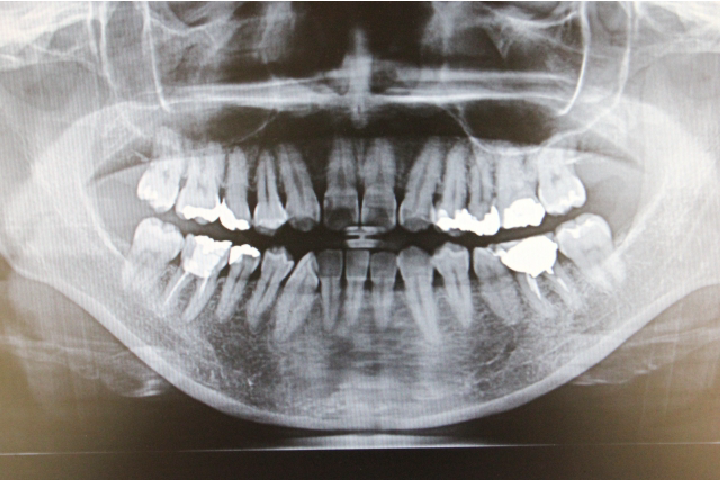

レントゲン検査

虫歯の有無に限らず、肉眼では見えない骨の状態や、埋まっている親知らずやお子さんの永久歯の数など多くのことが確認できます。そのため、治療だけでなく、検診やメンテナンスにおいても非常に大切な検査になります。